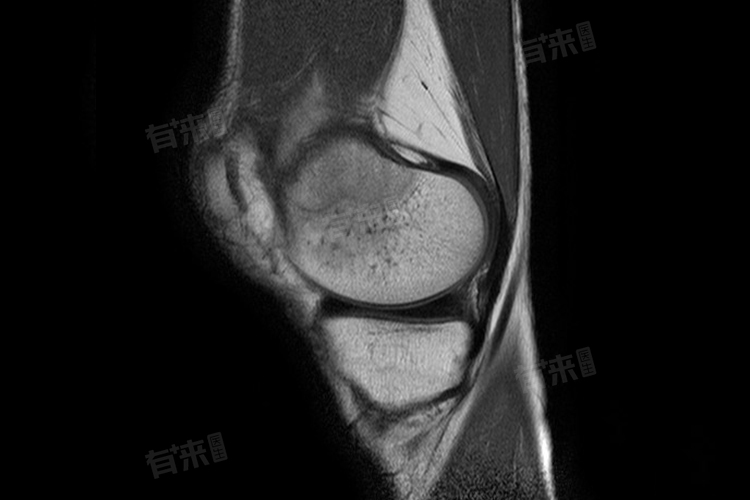

- 影像学检查:X线检查是基础检查手段,可初步观察骨骼形态;CT检查能更清晰地显示肿瘤的具体位置、范围,以及与周围骨骼的关系;MRI检查对软组织分辨率高,有助于明确肿瘤侵犯程度,是否累及骨髓、神经和血管。